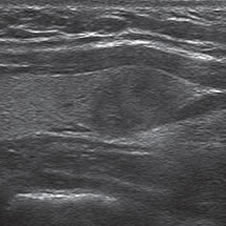

Los nódulos tiroideos se hacen palpables cuando alcanzan aproximadamente 10 mm de tamaño, dependiendo de su localización. Cuando la palpación era la principal manera de identificar nódulos, este diámetro era el límite para realizar una biopsia. Aunque las normas de la Asociación Americana de Endocrinólogos Clínicos (AACE) y la Asociación Americana de Tiroides (ATA) continúan usando 10 a 15 mm como el umbral práctico9,10 para seleccionar nódulos que necesitan de una PAAF, se ha demostrado que el tamaño no es un buen indicador para predecir malignidad. Son varios los trabajos que muestran que la prevalencia de cáncer es similar en nódulos mayores o menores de 10 mm11. La Sociedad de Radiólogos en Ultrasonido recientemente llegó al consenso de que, más que fijar un umbral de tamaño, debe usarse el aspecto ecográfico del nódulo como criterio de selección, tanto en el nódulo solitario como en la glándula multinodular4. En nódulos mayores de 10 mm no habría una diferencia significativa en el porcentaje de malignidad, aunque hay una tendencia que indicaría que la tasa de malignidad es más alta en nódulos mayores de 30-40 mm. El cáncer papilar menor de 10 mm se ha definido como microcarcinoma (Figura 1) y su frecuencia ha aumentado gradualmente en los últimos años12. Persiste el debate si este aumento es real o simplemente se debe al uso masivo de la ecografía cervical y la PAAF guiada por ecografía, lo que permite identificarlos precozmente. La presencia de múltiples nódulos no disminuye la probabilidad de cáncer tiroideo por paciente y el nódulo dominante por mayor tamaño no es necesariamente el que contiene el cáncer, ya que en aproximadamente un 30% el cáncer está en el nódulo no dominante4. Independiente del tamaño los nódulos casi completamente quísticos, sin otras características sospechosas, probablemente no requieren de biopsia.

Figura 1. Microcarcinoma de 8 mm.